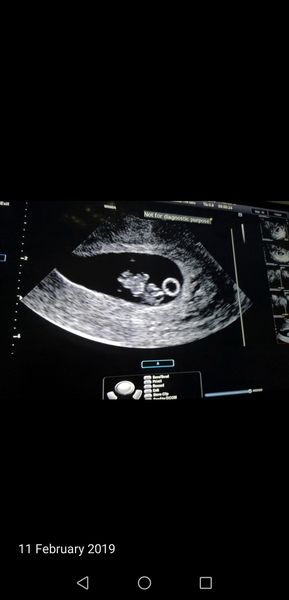

Hey, I was invited here and after reading all the messages and seeing the scan photos I just had to join in! So thank you for inviting me!

Had a scan on the 11th and was 8+1, and have to wait until 13 weeks for my 12 week scan. MW said because I have a retroverted uterus shed like to wait an extra week so we can see more but I'm soooo nervous. Xxxx